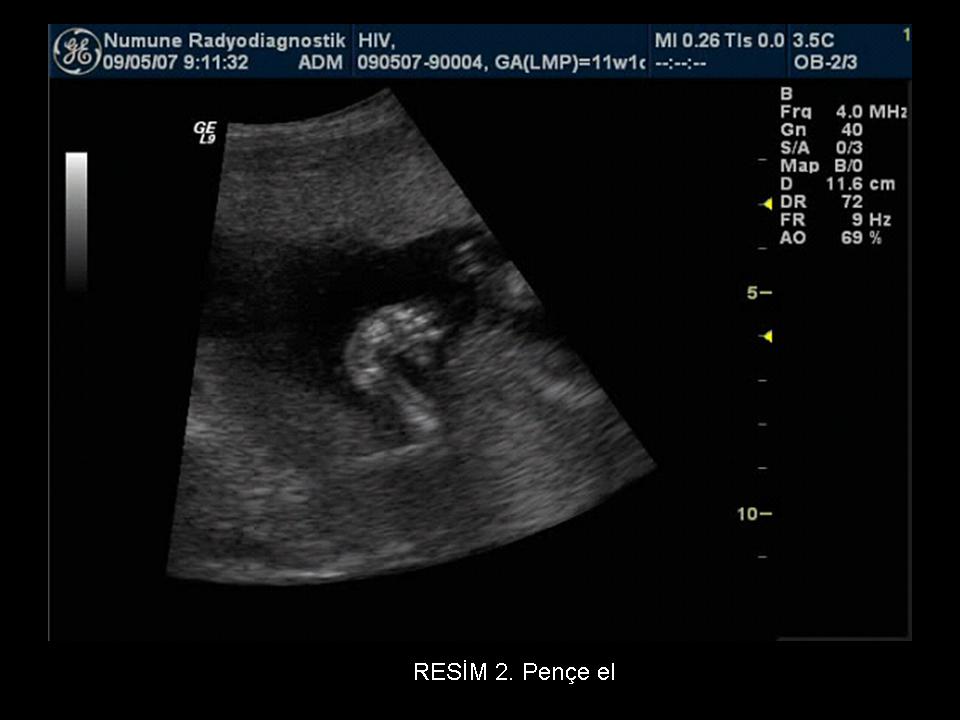

Yan duran bebeğin sırtı aşağıda olabilmektedir. Sıcak alanlar ve giysilerden kaynaklı değilse doktora götürülerek sebebin bulunması gerekir.